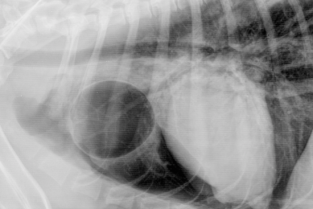

La radiographie thoracique reste le premier examen complémentaire lors de l'exploration des troubles respiratoires.

L'espace d'une journée, nous vous proposons d'analyser ensemble des images radiographiques normales et anormales du chat et du chien sur des stations de travail de l'AFVAC. Seront également abordées les images échographiques normales et anormales obtenues lors de l'examen du thorax.